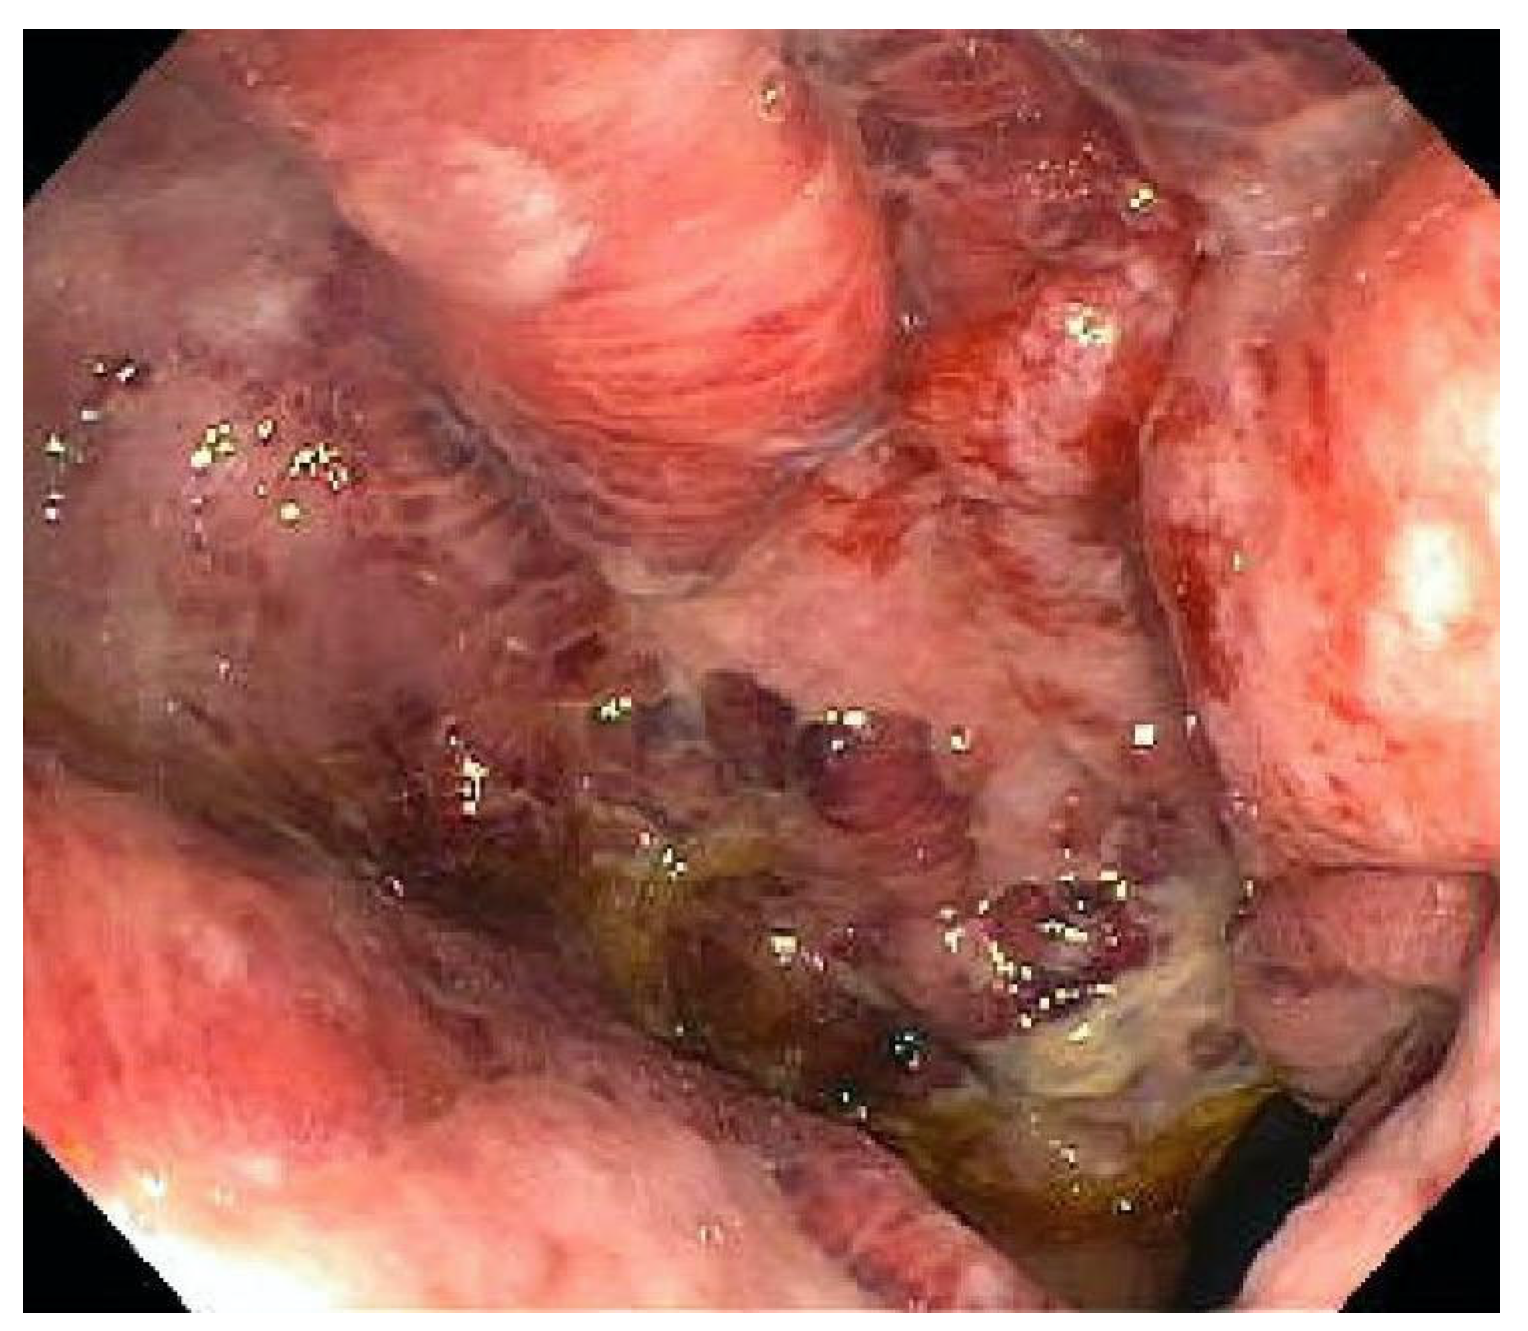

| Endoscopy | Punched-out ulcers, erosions, mucosal inflammation | Unable to distinguish between CMV colitis and IBD flare |